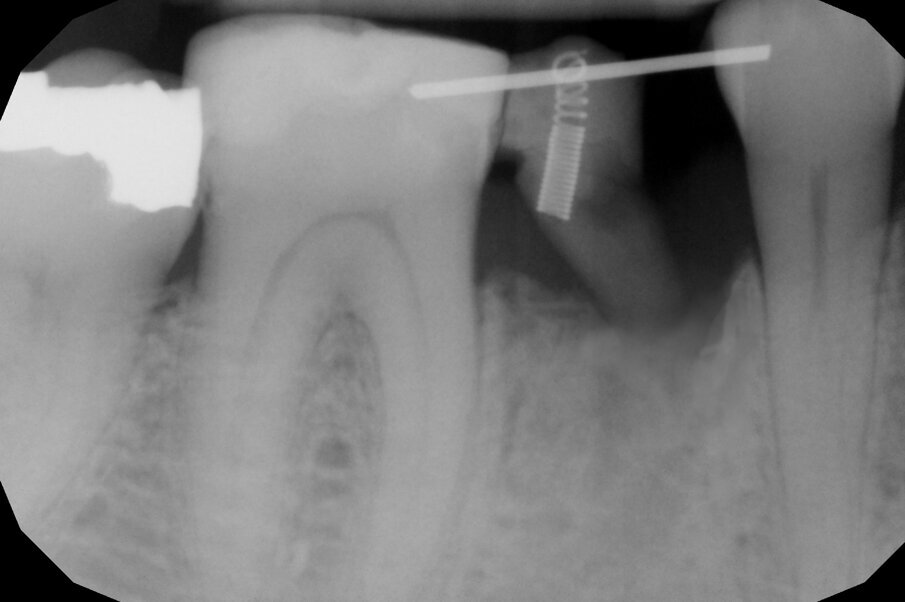

In questo caso clinico la difficoltà consisteva nel fatto che si è resa necessaria l’estrazione della metà mesiale della radice fratturata e quindi nel far compiere al frammento radicolare rimasto un movimento diagonale per mezzo del quale la porzione distale rimasta con il legamento parodontale avrebbe permesso una corretta rigenerazione tissutale ossea come indicato in rosso nell’immagine radiografica.

Per ottenere questo risultato nel gennaio 2021 è stato ancorato un segmento di arco in acciaio a sezione quadrata 0.021” x 0.025” agli elementi 4.4 e 4.6 per mezzo di composito. Il segmento è servito da ancoraggio per una molla con forza di trazione 150 g in posizione obliqua in senso disto-mesiale.